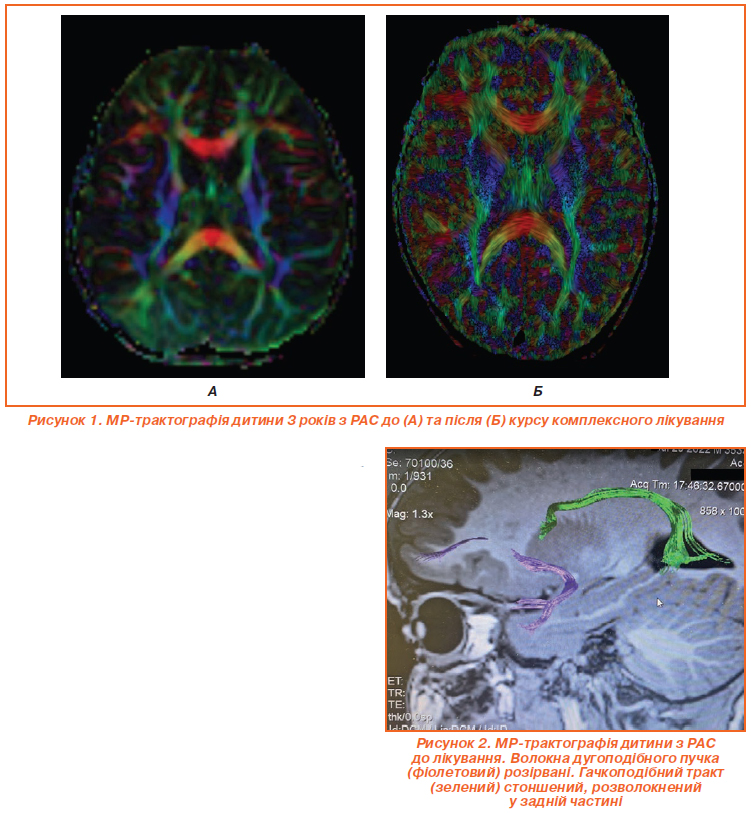

Оцінка мовленнєвого та когнітивного розвитку проводилася двічі, до початку терапії та після закінчення курсу лікування. Усім дітям було проведене комплексне обстеження, яке включало збір анамнезу, клініко-неврологічне обстеження, оцінку за шкалою Autism Treatment Evaluation Checklist (ATEC), ілюстрований словниковий тест Пібоді (Peabody Picture Vocabulary Test, PPVT) для оцінки пасивного словникового запасу; оцінку за шкалою поведінки Аченбаха (Child Behavior Checklist, CBCL), електроенцефалографію (ЕЕГ) та відео-ЕЕГ-моніторинг (зокрема, під час нічного сну), МРТ головного мозку та МР-трактографію дугоподібного (мовленнєвого) та гачкоподібного (когнітивного) трактів.

Для оцінки ефективності лікування застосовувалась МР-трактографія (рис. 1, 2). Рис. 1А відображає МР-трактографію мозку дитини 3 років з розладом аутистичного спектра (РАС) до лікування, видно характерні порушення в організації білої речовини. На аксіальному зрізі мозолисте тіло, представлене помаранчево-червоною дугоподібною структурою, виглядає стоншеним і асиметричним, з розривами трансверсальних волокон, що вказує на ослаблену міжпівкульну комунікацію, типову для РАС. Фронтальна ділянка з зеленими та жовтими асоціативними трактами, як-от superior longitudinal fasciculus, містить розірвані V-подібні структури з низькою щільністю, що корелює з труднощами в соціальній взаємодії та мовленні. У потиличних відділах візуалізуються фрагментовані inferior fronto-occipital fasciculus, а синьо-фіолетові кортикоспінальні тракти сформовані нерівномірно, що проявляється затримкою моторних навичок. Дугоподібні тракти (arcuate fasciculus) розірвані (рис. 2) та мають знижену фракційну анізотропію, що є маркером аномальної нейронної конективності при РАС.

Рисунок 1Б демонструє позитивну динаміку після курсу терапії, дані МР-трактографії вказують на поліпшення організації трактів. Мозолисте тіло стало більш цілісним і симетричним, з посиленою щільністю червоних волокон, що вказує на поліпшення інтеграції півкуль. Фронтальна ділянка містить відновлені superior longitudinal fasciculus та arcuate fasciculus з менш вираженими розривами, що сприяє поліпшенню соціальних та мовленнєвих навичок. Потилична ділянка містить відновлені inferior fronto-occipital fasciculus, які візуалізуються чіткіше. Збільшення фракційної анізотропії у дугоподібних та гачкоподібних трактах свідчить про високу нейропластичність дитячого мозку та ефективність терапії, хоча повна нормалізація потребує подальшого лікування.